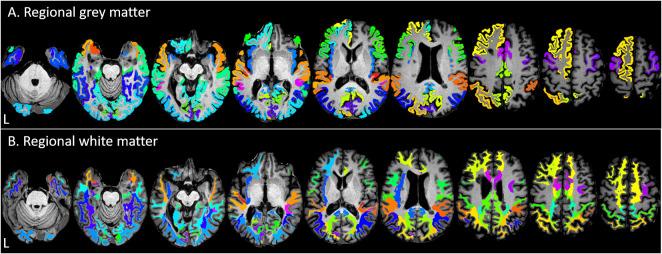

Recurrent neuroinflammation in relapsing-remitting MS (RRMS) is thought to lead to neurodegeneration, resulting in progressive disability. Repeated magnetic resonance imaging (MRI) of the brain provides non-invasive measures of atrophy over time, a key marker of neurodegeneration. This study investigates regional neurodegeneration of the brain in recently-diagnosed RRMS using volumetry and voxel-based morphometry (VBM). RRMS patients (N = 354) underwent 3T structural MRI <6 months after diagnosis and 1-year follow-up, as part of the Scottish multicentre 'FutureMS' study. MRI data were processed using FreeSurfer to derive volumetrics, and FSL for VBM (grey matter (GM) only), to establish regional patterns of change in GM and normal-appearing white matter (NAWM) over time throughout the brain. Volumetric analyses showed a decrease over time (q<0.05) in bilateral cortical GM and NAWM, cerebellar GM, brainstem, amygdala, basal ganglia, hippocampus, accumbens, thalamus and ventral diencephalon. Additionally, NAWM and GM volume decreased respectively in the following cortical regions, frontal: 14 out of 26 regions and 16/26; temporal: 18/18 and 15/18; parietal: 14/14 and 11/14; occipital: 7/8 and 8/8. Left GM and NAWM asymmetry was observed in the frontal lobe. GM VBM analysis showed three major clusters of decrease over time: 1) temporal and subcortical areas, 2) cerebellum, 3) anterior cingulum and supplementary motor cortex; and four smaller clusters within the occipital lobe. Widespread GM and NAWM atrophy was observed in this large recently-diagnosed RRMS cohort, particularly in the brainstem, cerebellar GM, and subcortical and occipital-temporal regions; indicative of neurodegeneration across tissue types, and in accord with limited previous studies in early disease. Volumetric and VBM results emphasise different features of longitudinal lobar and loco-regional change, however identify consistent atrophy patterns across individuals. Atrophy measures targeted to specific brain regions may provide improved markers of neurodegeneration, and potential future imaging stratifiers and endpoints for clinical decision making and therapeutic trials.

复发缓解型多发性硬化症(RRMS)中反复发生的神经炎症被认为会导致神经退行性变,从而导致进行性残疾。对大脑进行重复磁共振成像(MRI)可随时间提供萎缩的非侵入性测量,这是神经退行性变的关键标志物。本研究使用体素形态计量学(VBM)对近期诊断的 RRMS 患者的大脑进行区域性神经退行性变研究。RRMS 患者(N=354)在诊断后 6 个月内和 1 年随访期间接受了 3T 结构 MRI,这是苏格兰多中心“未来 MS”研究的一部分。MRI 数据使用 FreeSurfer 进行处理,以得出体积测量值,并使用 FSL 进行 VBM(仅灰质(GM)),以建立整个大脑 GM 和正常外观的白质(NAWM)随时间变化的区域性模式。体积分析显示,随着时间的推移(q<0.05),双侧皮质 GM 和 NAWM、小脑 GM、脑干、杏仁核、基底节、海马体、伏隔核、丘脑和腹侧间脑的体积减少。此外,分别在以下皮质区域中,NAWM 和 GM 体积减少:额叶:26 个区域中有 14 个和 16/26;颞叶:18/18 个和 15/18;顶叶:14/14 个和 11/14;枕叶:7/8 个和 8/8。左侧 GM 和 NAWM 不对称发生在额叶。GM VBM 分析显示,随时间减少的三个主要聚类:1)颞叶和皮质下区域,2)小脑,3)前扣带和辅助运动皮质;以及枕叶内的四个较小聚类。在这个大型最近诊断的 RRMS 队列中观察到广泛的 GM 和 NAWM 萎缩,特别是在脑干、小脑 GM 和皮质下及颞枕叶区域;表明各种组织类型的神经退行性变与早期疾病的有限先前研究一致。体积和 VBM 结果强调了纵向脑叶和局部区域变化的不同特征,但在个体之间识别出一致的萎缩模式。针对特定脑区的萎缩测量可能提供更好的神经退行性变标志物,并为临床决策和治疗试验提供潜在的未来成像分层和终点。